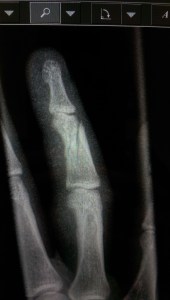

This is a “mildly comminuted and slightly displaced complete transverse fracture of the middle phalanx of the right 4th finger, with associated soft tissue swelling.” In translation I snapped my finger in half like a Q-tip.